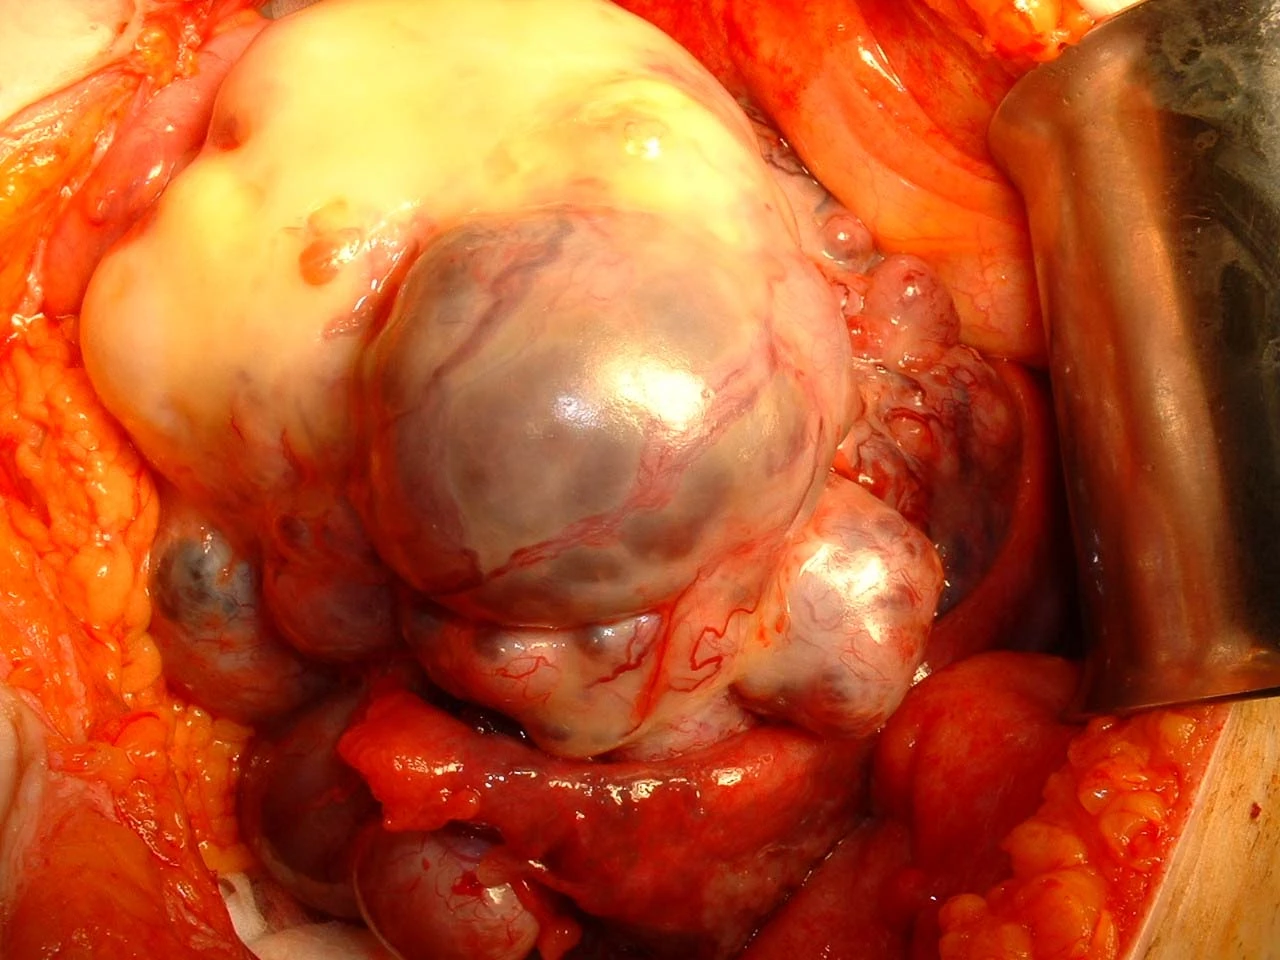

(Kiến Thức) - Các nhà khoa học Mỹ đã phát hiện ra cách ngăn tế bào ung thư di căn rất hiệu quả.

Theo các nhà khoa học thì cách này có thể "khóa chặt" tế bào ung thư tại chỗ, ngăn không cho chúng lây lan khắp cơ thể. Quá trình ngăn ung thư di căn này được gọi là autophagy tế bào ung thư.

Trong phương pháp này, autophagy đóng vai trò vệ sinh tế bào khỏe mạnh, phá vỡ thành phần tế bào không cần thiết thành khối năng lượng hay protein để sử dụng, giúp loại bỏ tác nhân gây bệnh và chống lại bệnh ung thư.

Cũng trong quá trình này sẽ có các gene liên quan tới autophagy bị đánh bật ra khỏi tế bào ung thư, và chúng sẽ ngăn cản tế bào di chuyển.

Giáo sư MacLeod thuộc ĐH Chicago người đứng đầu nghiên cứu này chia sẻ: "Tôi cho rằng, việc ức chế autophagy sẽ có thể ngăn chặn sự di căn của khối u. Đây sẽ là phương pháp hiệu quả giúp ngăn chặn sự lây lan của bệnh ung thư hoặc chứng di căn trong thời gian tới".

Nếu bạn bị bệnh ung thư, đặc biệt là khi nó đã di căn thì việc điều trị sẽ trở nên vô cùng khó khăn. Do đó, việc có thể kìm hãm sự lây lan tế bào ung thư ra các bộ phận khác là cực kỳ quan trọng, và là bước nhảy vọt trong chữa trị bệnh ung thư.

Hiện tại, mặc dù chưa được thử nghiệm trên người những kết quả sau khi chuyên gia tiến hành thử nghiệm điều trị bằng phương pháp này trên chuột có tế bào ung thư rất khả quan. Các nhà khoa học ghi nhận được rằng những khối u lớn nhưng không lây lan đến phổi, gan hay xương.

Với nghiên cứu này hi vọng trong thời gian tới, việc chữa trị bệnh ung thư cho con người trở nên dễ dàng và hiệu quả hơn.